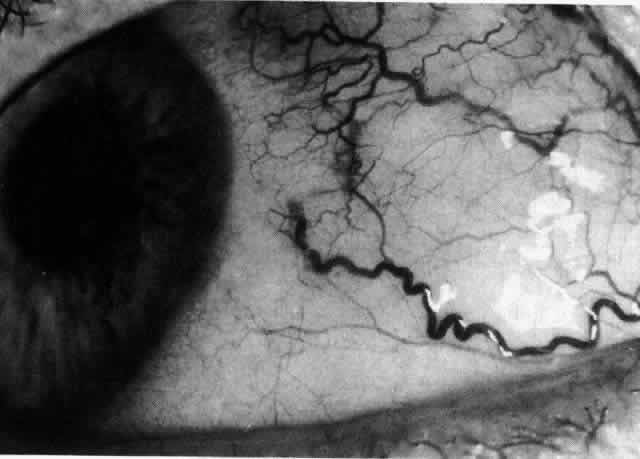

ARTERIAL PHASE Anterior Episcleral Arterial Circle The anterior ciliary arteries run radially toward the limbus within Tenon's capsule, giving few, if any, branches until they reach the anterior part of the globe. Their positions are very variable, and they do not always follow the rectus muscles. They bifurcate 2 to 5 mm behind the limbus, and each division runs forward and circumferentially to anastomose with a branch from an adjacent artery. This results in an anterior episcleral arterial circle (Figs. 3 through 5). The divisions of the anterior ciliary arteries are typically superficial at their origins but run deeper at their anastomoses. They occasionally dip too deep to be seen in fluorescein angiograms (Fig. 6).

From the anterior episcleral arterial circle, four distinct circulations are supplied: episcleral, anterior conjunctival, limbal, and iris. Episcleral Circulation Immediately after their origin by bifurcation of the anterior ciliary arteries, the contributions to the anterior episcleral circle divide again to give recurrent branches that run posteriorly and subdivide to form a netlike episcleral plexus (see Fig. 5; Fig.7). The variability of the positioning of the anterior ciliary arteries inevitably leaves large areas of episclera far from such an arterial supply (see Figs. 4, 6, and 7). These areas receive other posterior branches from the episcleral circle. Where the circle runs deep within the sclera, such branches appear as isolated perforating vessels (see Fig. 6). They fill very shortly after the episcleral circle, and they also divide repeatedly as they run posteriorly.